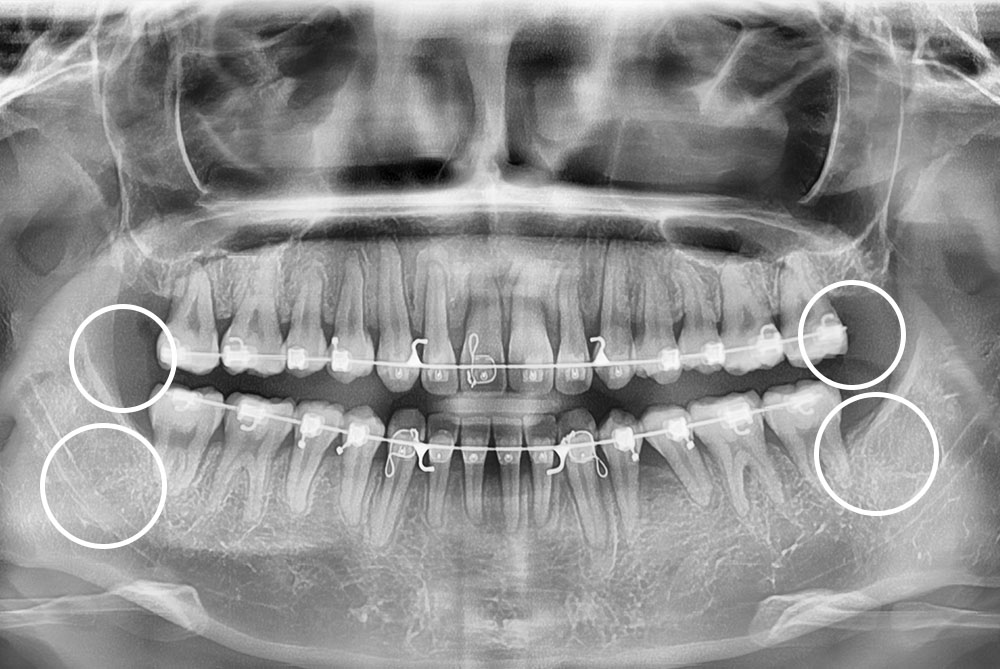

[사랑니] 매복 사랑니 발치

치료후 : 2023-06-12

세종치과는 구강악안면외과학 박사이신 원장님이 발치하는 치과입니다.